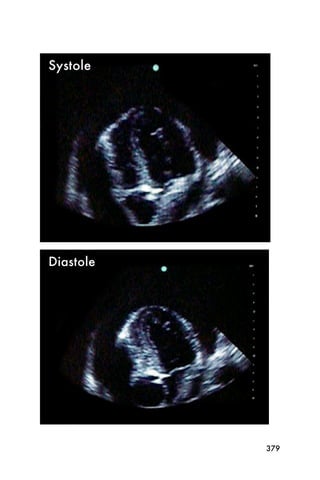

The parasternal short axis view is most useful for

evaluating the systolic function of the heart measured as

ejection fraction (EF).

Again, the ejection fraction is evaluated by the operator

and is usually just estimated. Estimating the ejection

fraction comes with practice, but after reviewing a few

echocardiograms and performing a few echocardio-

grams, the operator should be able to identify patients

with a normal EF and patients with a low EF.